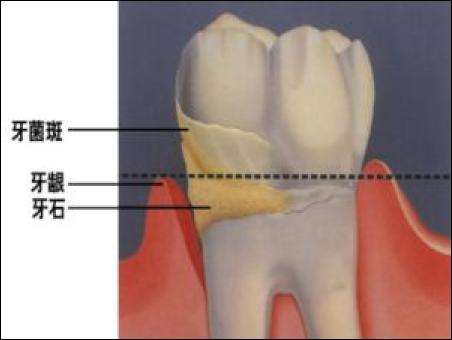

其實,這是人類長期進化的結(jié)果。在古代,我們的食物很粗糙,因此,我們需要智齒來幫助我們研磨食物。因此,那個時候,人一般在20多點就長出智齒。智齒,通常稱智慧之齒,代表人的智力和閱歷的身心成熟。但是,隨著我們的生活水平的不斷提高,我們的食物被加工的過分精細,經(jīng)常用不到智齒,也能滿足我們的日常生活需要。根據(jù)"用進廢退”的原理,智齒慢慢地就不再需要了,因此,很多人智齒不僅長的晚,而且還長不好,經(jīng)常的發(fā)炎,俗稱智齒冠周炎,嚴重的會影響到我們的生活和健康,因此,現(xiàn)在絕大多數(shù)人的智齒最后都需要拔掉,因為我們不需要了。大家可以仔細回想一下,在改革開放前的三十年,我們的食物構(gòu)成中,粗糧、豆類很多,我們用第三磨牙的地方自然也很多,而且食物因為顆粒大,也不容易塞牙。但是,現(xiàn)在,我們吃的精加工的食物殘渣,很容易掛在牙齒周圍,而這些軟垢和我們口腔的唾液混和在一起,就容易形成牙結(jié)石,久而久之,就掛滿了我們的牙齦上下,引起發(fā)炎。長期的慢性發(fā)炎,導致我們的牙槽骨被吸收,牙齒就會越變越長,最后掛掉。大家看一組照片。

牙結(jié)石是如何附著在牙齦周圍的